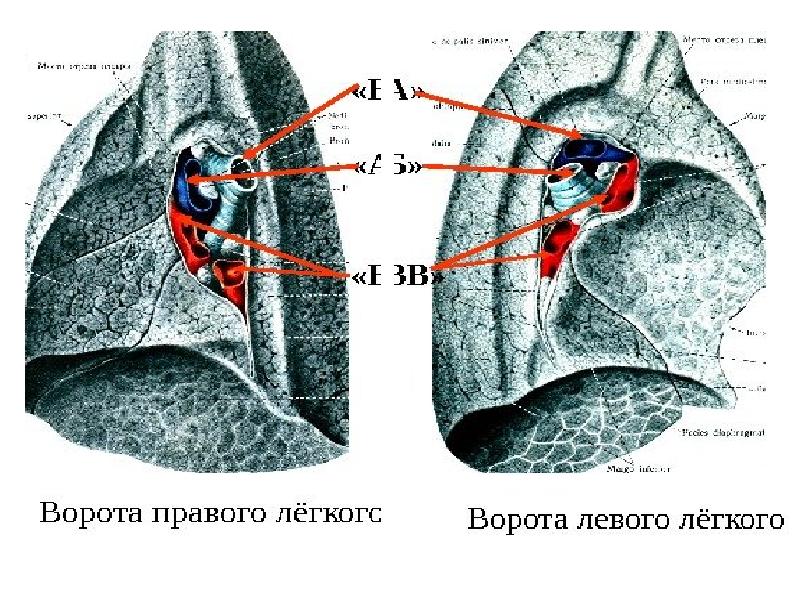

Анатомические изображения сегментов легких различных животных

Раздел: Другие животные